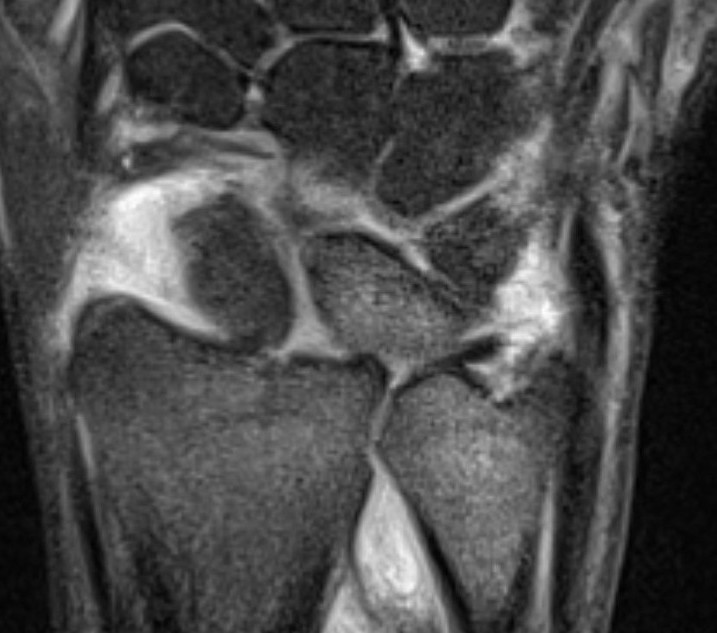

Isolated dorsal dislocation DRUJ

Isolated dorsal DRUJ instability with ulna sided TFCC tear

MRI demonstrating dorsal distal ulna subluxation associated with significant ligament disruption